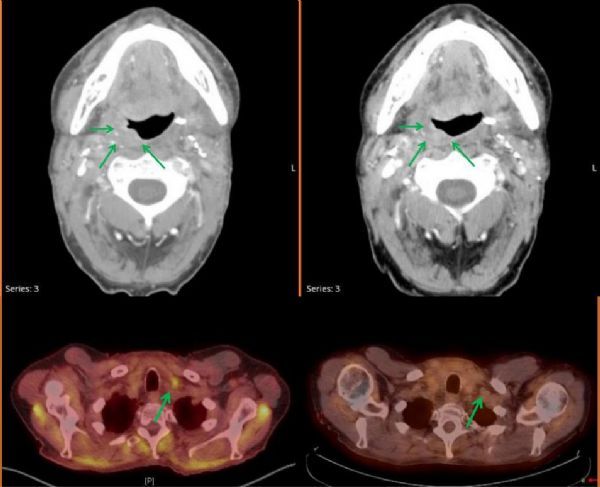

转移性头颈癌患者在接受PD-1抗体治疗后,获得完全缓解(图片来源 clincancerre)

该研究的主要负责人Charu Aggarwal博士表示,先前其利用一个剂量的疫苗进行试验并未观察到这种浸润肿瘤的现象。此次的研究结果无疑为利用针对HPV等特定致癌靶点的免疫治疗方法打开了一扇大门。而且这款疫苗的耐受性也很好,患者仅在注射部位发生手臂疼痛,没有任何严重副作用的报告。另外,论文作者还特别描述了一名患者的病例,该患者在手术前接受了一剂疫苗接种,在治疗后7个月出现转移复发,此时他接受了PD-1抑制剂Nivolumab并持续完全缓解。两年后,仍然没有任何疾病迹象。对此,Aggarwal表示:“这种反应表明该疫苗可能以某种方式引发免疫系统,或增强后续抗PD-1治疗的效果。”